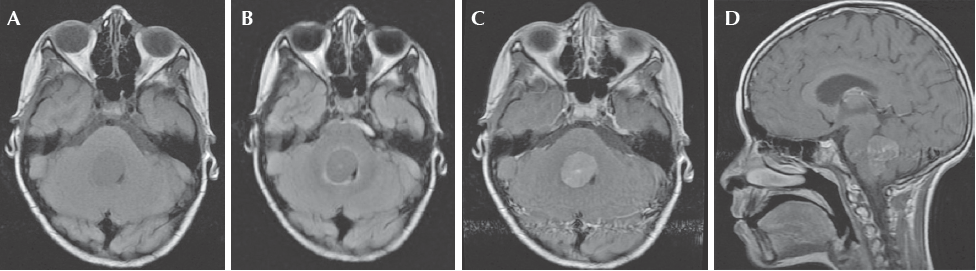

Niña de diez años, diez meses de edad, cuyo padecimiento tenía un mes de evolución e inició con vómito y ataque al estado general, se le trató como enfermedad acidopéptica sin mejoría. Tiempo después, la paciente presentó alteración de la marcha, por lo que se realizó tomografía axial computada de cráneo que mostró una zona hiperdensa en el cuarto ventrículo, que medía 2.5 x 3.5 cm y desplazaba rostralmente al tallo cerebral (Figura 1) La resonancia magnética mostró una lesión del cuarto ventrículo hipointensa homogénea, extraaxial, que reforzaba de forma difusa al contraste (gadolinio); sin infiltración aparente del cuarto ventrículo ni del pedúnculo cerebeloso por lo que se sospechó diagnóstico de meduloblastoma. (Figura 2) Lo anterior llevó a decidir una resección quirúrgica de la lesión en un 90% aproximadamente. Un informe transquirúrgico de patología informó de un tumor de células pequeñas, redondas y azules (Figura 3a). El informe histopatológico final fue de neoplasia maligna de estirpe linfoide con marcadores inmunohistoquímicos positivos para CD-45 (Figura 3b) y CD-20 (Figura 3c), base para el diagnóstico de linfoma difuso de células grandes B.

Figura 3 Cortes histológicos. A) Tinción de hematoxilina-eosina: neoplasia maligna de estirpe linfoide que crece en láminas sólidas, células de tamaño mediano a grande, escaso citoplasma, núcleos ovales, cromatina abierta, nucléolo prominente; estas células alternan con linfocitos maduros residuales. B) CD45 (antígeno común leucocitario) positivo intensa y difusamente decorando la membrana celular. C) CD20 positivo intensamente en la membrana de los linfocitos B.